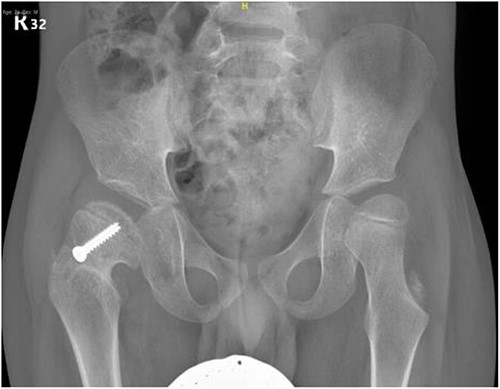

A 5-year-old independent ambulatory Middle Eastern boy with CP who was born preterm and developed grade III intraventricular haemorrhage and periventricular leucomalacia and was on AEDs, including valproic acid (VPA) and levetiracetam (LEV), for >3 years and was controlled over the last year (no history of seizure attack) presented to the emergency room (ER) with right hip pain and inability to bear weight for 4 weeks; the patient had no history of fever or trauma. Physical examination shows a thin, the weight is 12 kg, the height is 101 cm, vital signs within the normal range, tenderness over the right hip, and external rotation of the right hip, with restricted hip mobility. A radiological study was performed ~3 months before the patient presented to the ER for follow-up examination of a left hip coxa valgus deformity with no apparent abnormalities in the right hip (Fig. 1). Initial imaging studies conducted in the ER showed an anterior–posterior view of the pelvic radiograph, revealing Klein’s line [13] not intersecting the capital femoral epiphysis (Fig. 2), and frog-leg lateral view radiograph of the right hip (Fig. 3) confirmed SCFE and Southwick’s slip angle [13] of ~50° (moderate). Laboratory findings were clear for endocrine and renal diseases or infection, except for low vitamin D (total 25-OH Vitamin D: 43.4 nmol/L), suggesting vitamin D insufficiency. The diagnosis was confirmed with clinical and radiological studies as right-sided unstable SCFE requiring surgery. Surgical intervention was performed with percutaneous in situ fixation using a single fully threaded 4.5-mm cannulated screw (Fig. 4). Postsurgical rehabilitation included non-weight-bearing right lower extremities for 6 weeks. Regular follow-up with serial radiology studies showed stable fixation with no migration of screw or further slippage at 6 weeks (Fig. 5) and 3 (Fig. 6), 15 (Fig. 7), and 36 months (Fig. 8). During follow-up, a painless range of motion in the right hip was observed, with full weight-bearing and resumption of his usual activities with no complaints.

Pelvic anterior–posterior radiograph immediately after in situ fixation with single cannulate screw.